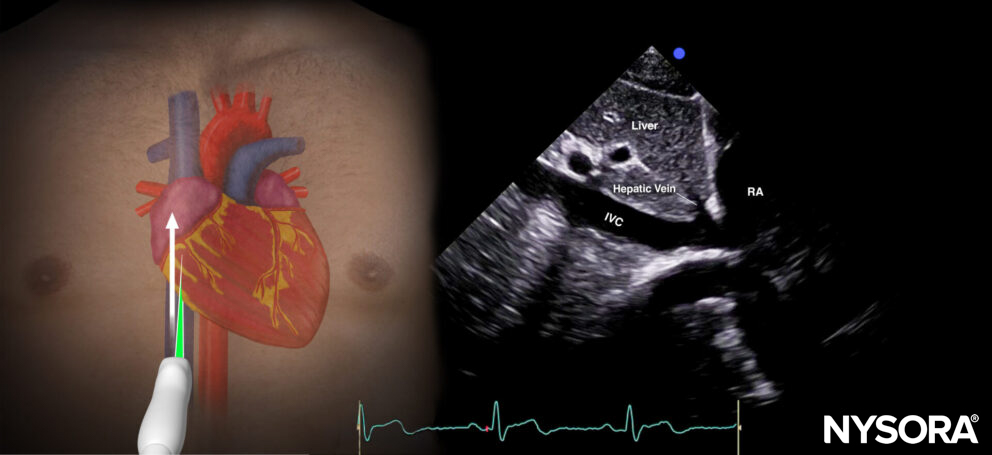

Inferior vena cava view (IVC)

Positioning:

Place the transducer perpendicular to the skin in the subcostal position, with the index marker toward the patient’s left. After visualizing the inferior vena cava and the aorta, focus the ultrasound beam on the inferior vena cava and rotate the index marker 90 degrees counterclockwise (toward the head). Try to visualize its junction with the right atrium by rocking the transducer.

Sonoanatomy:

The inferior vena cava view cuts through the inferior vena cava and the right atrium.

Sonoanatomy of the inferior vena cava view. Inferior vena cava (IVC), right atrium (RA), hepatic vein(sometimes), liver.

Practical use:

- Volume status (inferior vena cava size variation)